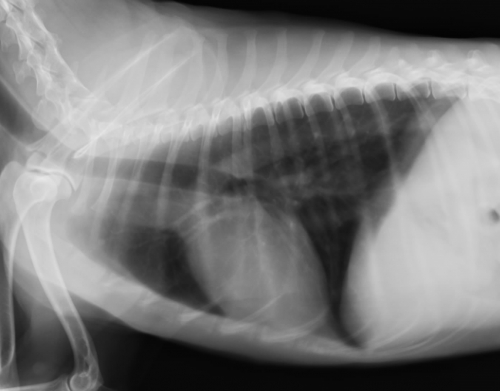

下の写真が肺転移の一例です。(右写真が正常です。)